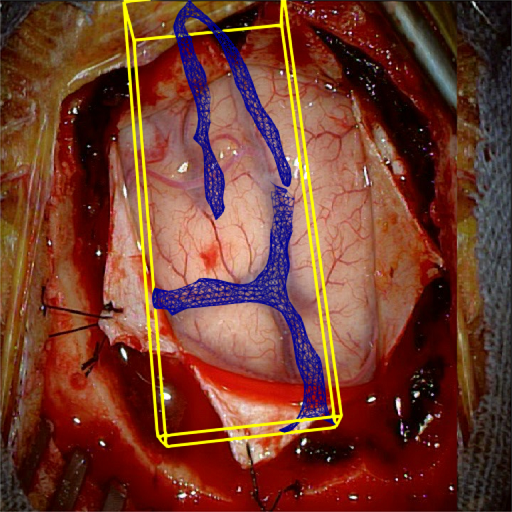

Fig. 5 shows our results as Augmented Reality views with bounding boxes and overlaid meshes. Our method produced visually consistent alignments for all 6 clinical cases without the need for initial registration. Because our current method does not account for brain-shift deformation, our method produced some misalignment errors. However, in all cases, our predictions are similar to the ground truth.